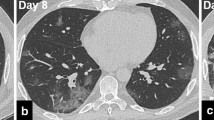

Images were reviewed and processed in an AW Volumeshare 4 workstation (General Electric Healthcare, Chicago, IL, USA) by 2 different radiologists, F.P. and L.B., with 10 and 15 years of experience in thoracic imaging, respectively. The radiologists were blinded to the clinical and laboratory data. Volume of disease (VoD) was extracted using the “autoselect” function and the result was expressed in cubic centimeters. The radiologist selected the desired opacity and voxels with similar pixel values were automatically extracted (region growing). Corrections had to be made in cases of pulmonary consolidations adjacent to the chest wall or mediastinum. The duration of the segmentation task ranged from 2 to 5 min. Figures 2 and 3 depict segmentation examples. The remaining CT-derived data was obtained and expressed using a slightly modified version of the descriptive system used by Inui et al. [14]: involved lungs, gradient, distribution of disease, CT pattern type, predominant type of opacity, reverse halo, linear opacities, and nodules. We also registered the following secondary findings: enlarged thoracic lymph nodes, presence of pleural effusion or thickening, coronary and/or aortic calcification, chronic lung disease (emphysema or fibrosis), and other significant findings (such as pneumothorax or pneumomediastinum).